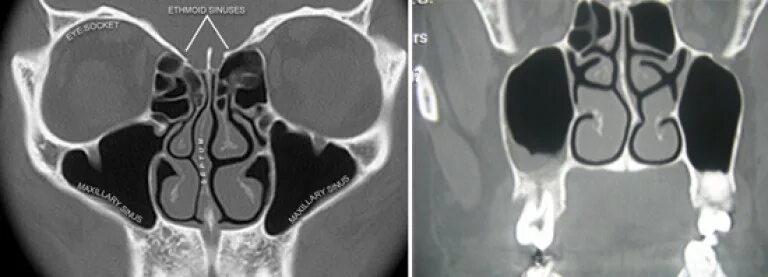

Синусит на кт